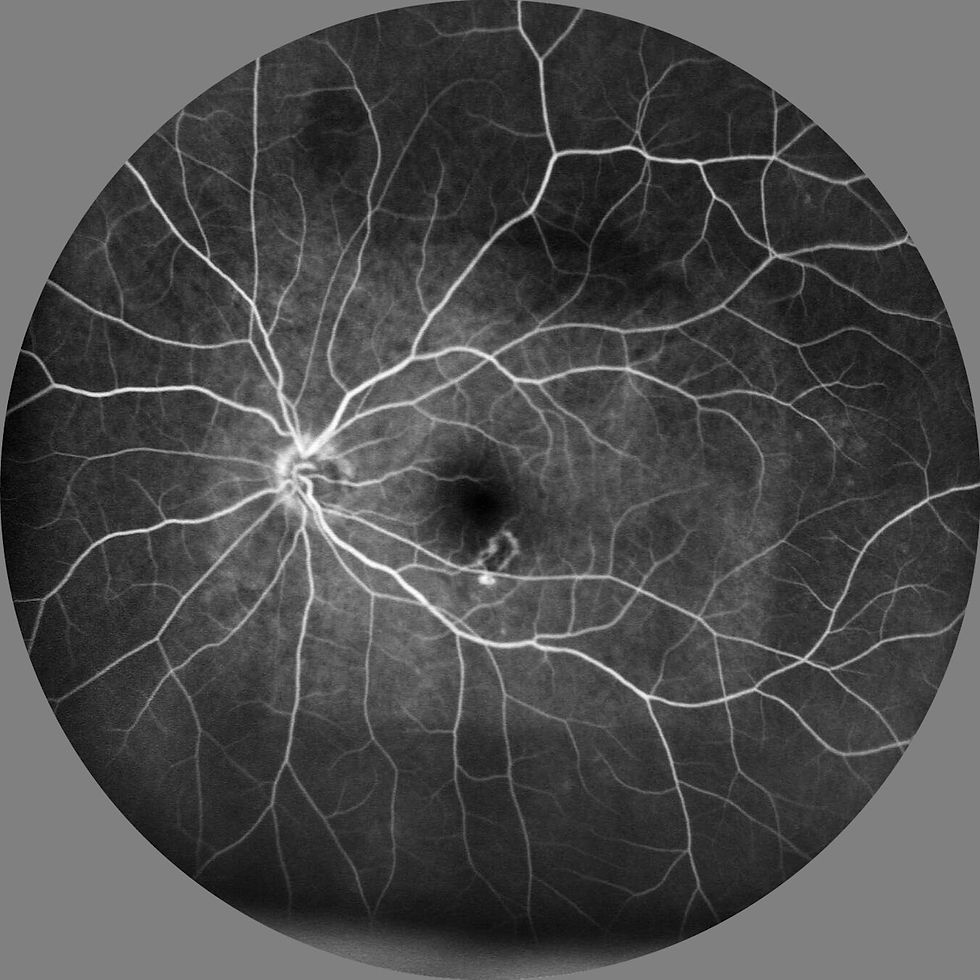

There are two commonly used drugs for age-related macular degeneration, also known as AMD.

These two treatments contain anti-VEGF drugs - this blocks the vascular endothelial growth factor, which stops abnormal blood vessel growth and reduce fluid leakage and swelling.

Vabysmo and Eylea can also be used for other eye conditions such as Diabetic Macular Oedema, Diabetic Retinopathy, and Oedema following a Retinal Vein Occlusion. Eylea may also be used for Myopic Choroidal Neovascularisation.